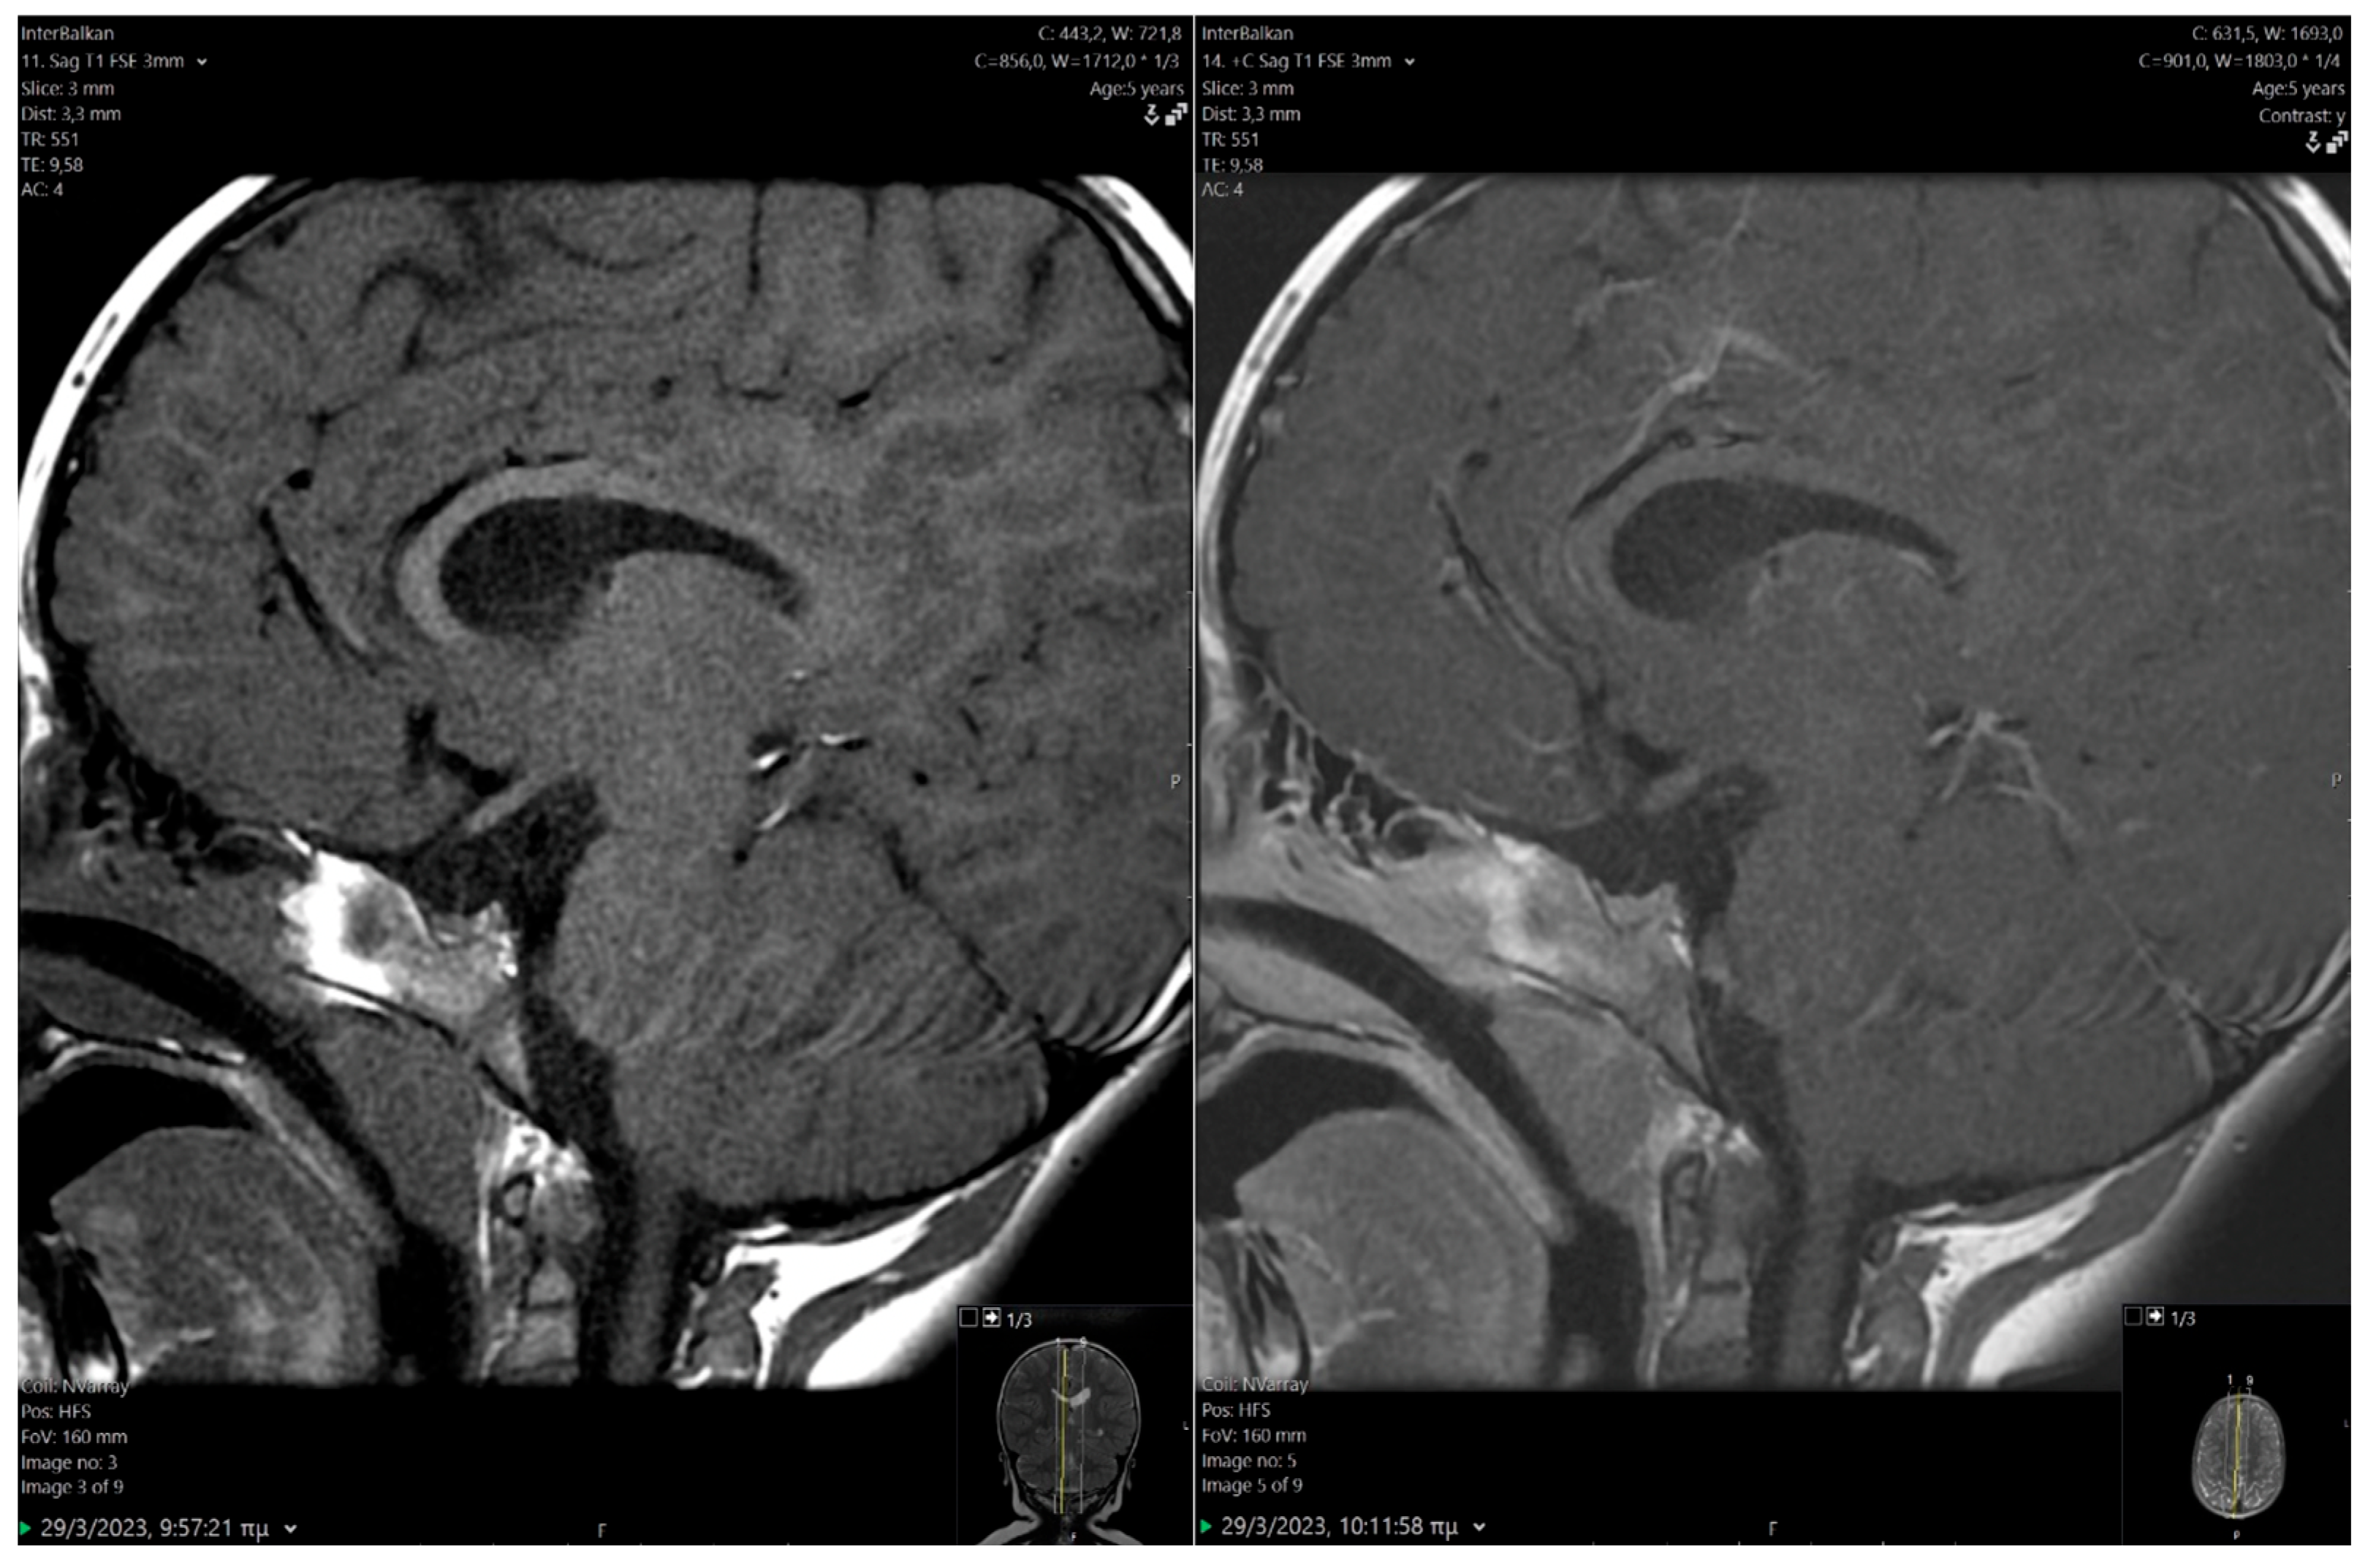

2.1. Clinical Findings/Diagnostic Assessment